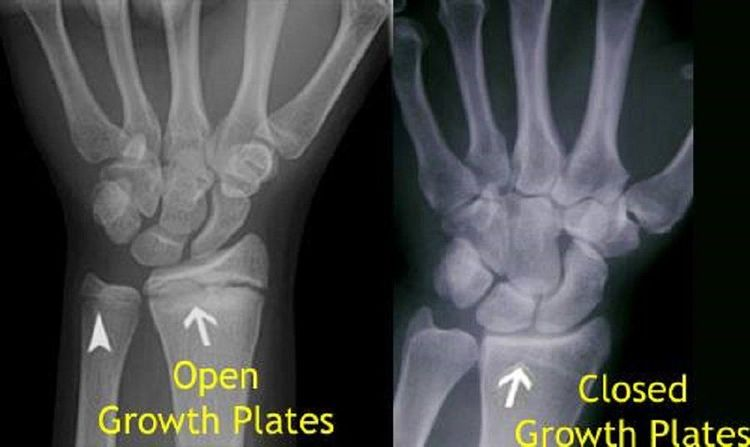

Bone plates gh and height

are my wrist bone plates closed ? I’m 18 and do you think any of my other plates would be open, would taking gh infinigrib and an ai benefit me at this point. Or would it cause harm to me from side affects I hear if you take gh after closure it may just harm you more then it helps u and for me I’m not for sure if all my plates are closed should I hop on?

Yours appear to be closed to me.

they’re closed but u should get ur knees checked, they are your last hope, if they’re open u might have a small window of growth left